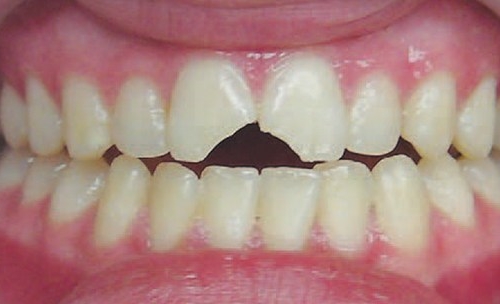

Doğru diaqnostika, müalicə planlaması və sonrakı dönəmdə izləmə uğurlu müalicəyə aparan ən başlıca faktorlardır. Diş travmaları və yaralanmaları tək diş bölgəsini əhatə edən məhdud, eyni zamanda çoxsaylı diş bölgəsini və çənənin alveol darağını əhatə edəcək qədər yayılmış formada rast gəlinə bilir. Çoxsaylı diş zədələnmələrində çox zaman fərqli dişlərdə fərqli növ zədələnmə şəkili aşkar edilə bilir ki, bu da hər bir dişə individual yanaşma və müalicə metodu tələb edir.